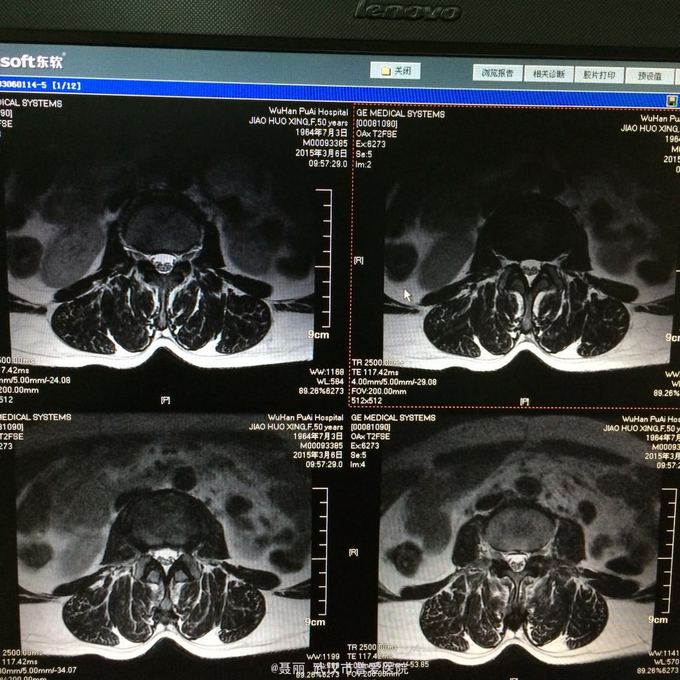

:L4/5棘突间轻压痛,叩痛,棘间左侧椎旁压痛;双下肢肌力、肌张力正常,病理反射未引出。 门诊资料:外院行腰椎CT检查示:L3-S1椎间盘膨出,L4椎弓崩裂并向前滑脱(重度)椎管狭窄。 入

入院诊断:、腰椎滑脱(L4/5 峡部裂性) 诊疗计划:1:完善有关检查2卧床休息,行改善微循环、3.腰椎后路复位减压植骨融合术

行改善微循环、3.腰椎后路复位减压植骨融合术 腰椎滑脱(L4/5 Ⅱ度)、腰椎管狭窄症(L3/4)、腰椎间盘突出症(L5/S1)查体双下肢感觉、活动无明显异常。双下肢末梢血液循环可。换药见伤口对合良好,无明显红肿渗出。伤口已拆线。嘱加强双下肢活动及功能锻炼,避免下肢深静脉血栓,主动及被动四肢活动,预防血静脉及床褥形成,加强腰背肌锻炼,适量康复功能锻炼。一个月后来复查伤口愈合好,疼痛没有,活动可